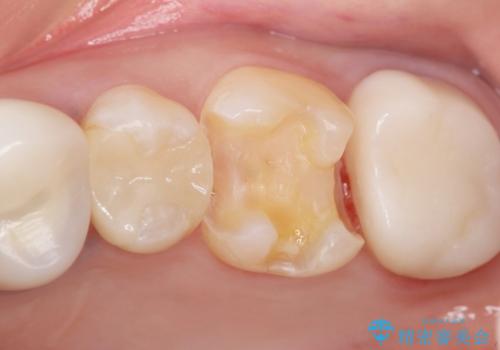

- 奥歯がたまにしみることを主訴に来院された患者様です。

精査したところ、奥歯のメタルインレー(銀の詰め物)の下でう蝕が広がっていました。

う蝕を丁寧に除去したのち、セラミックインレーによる補綴治療を行いました。